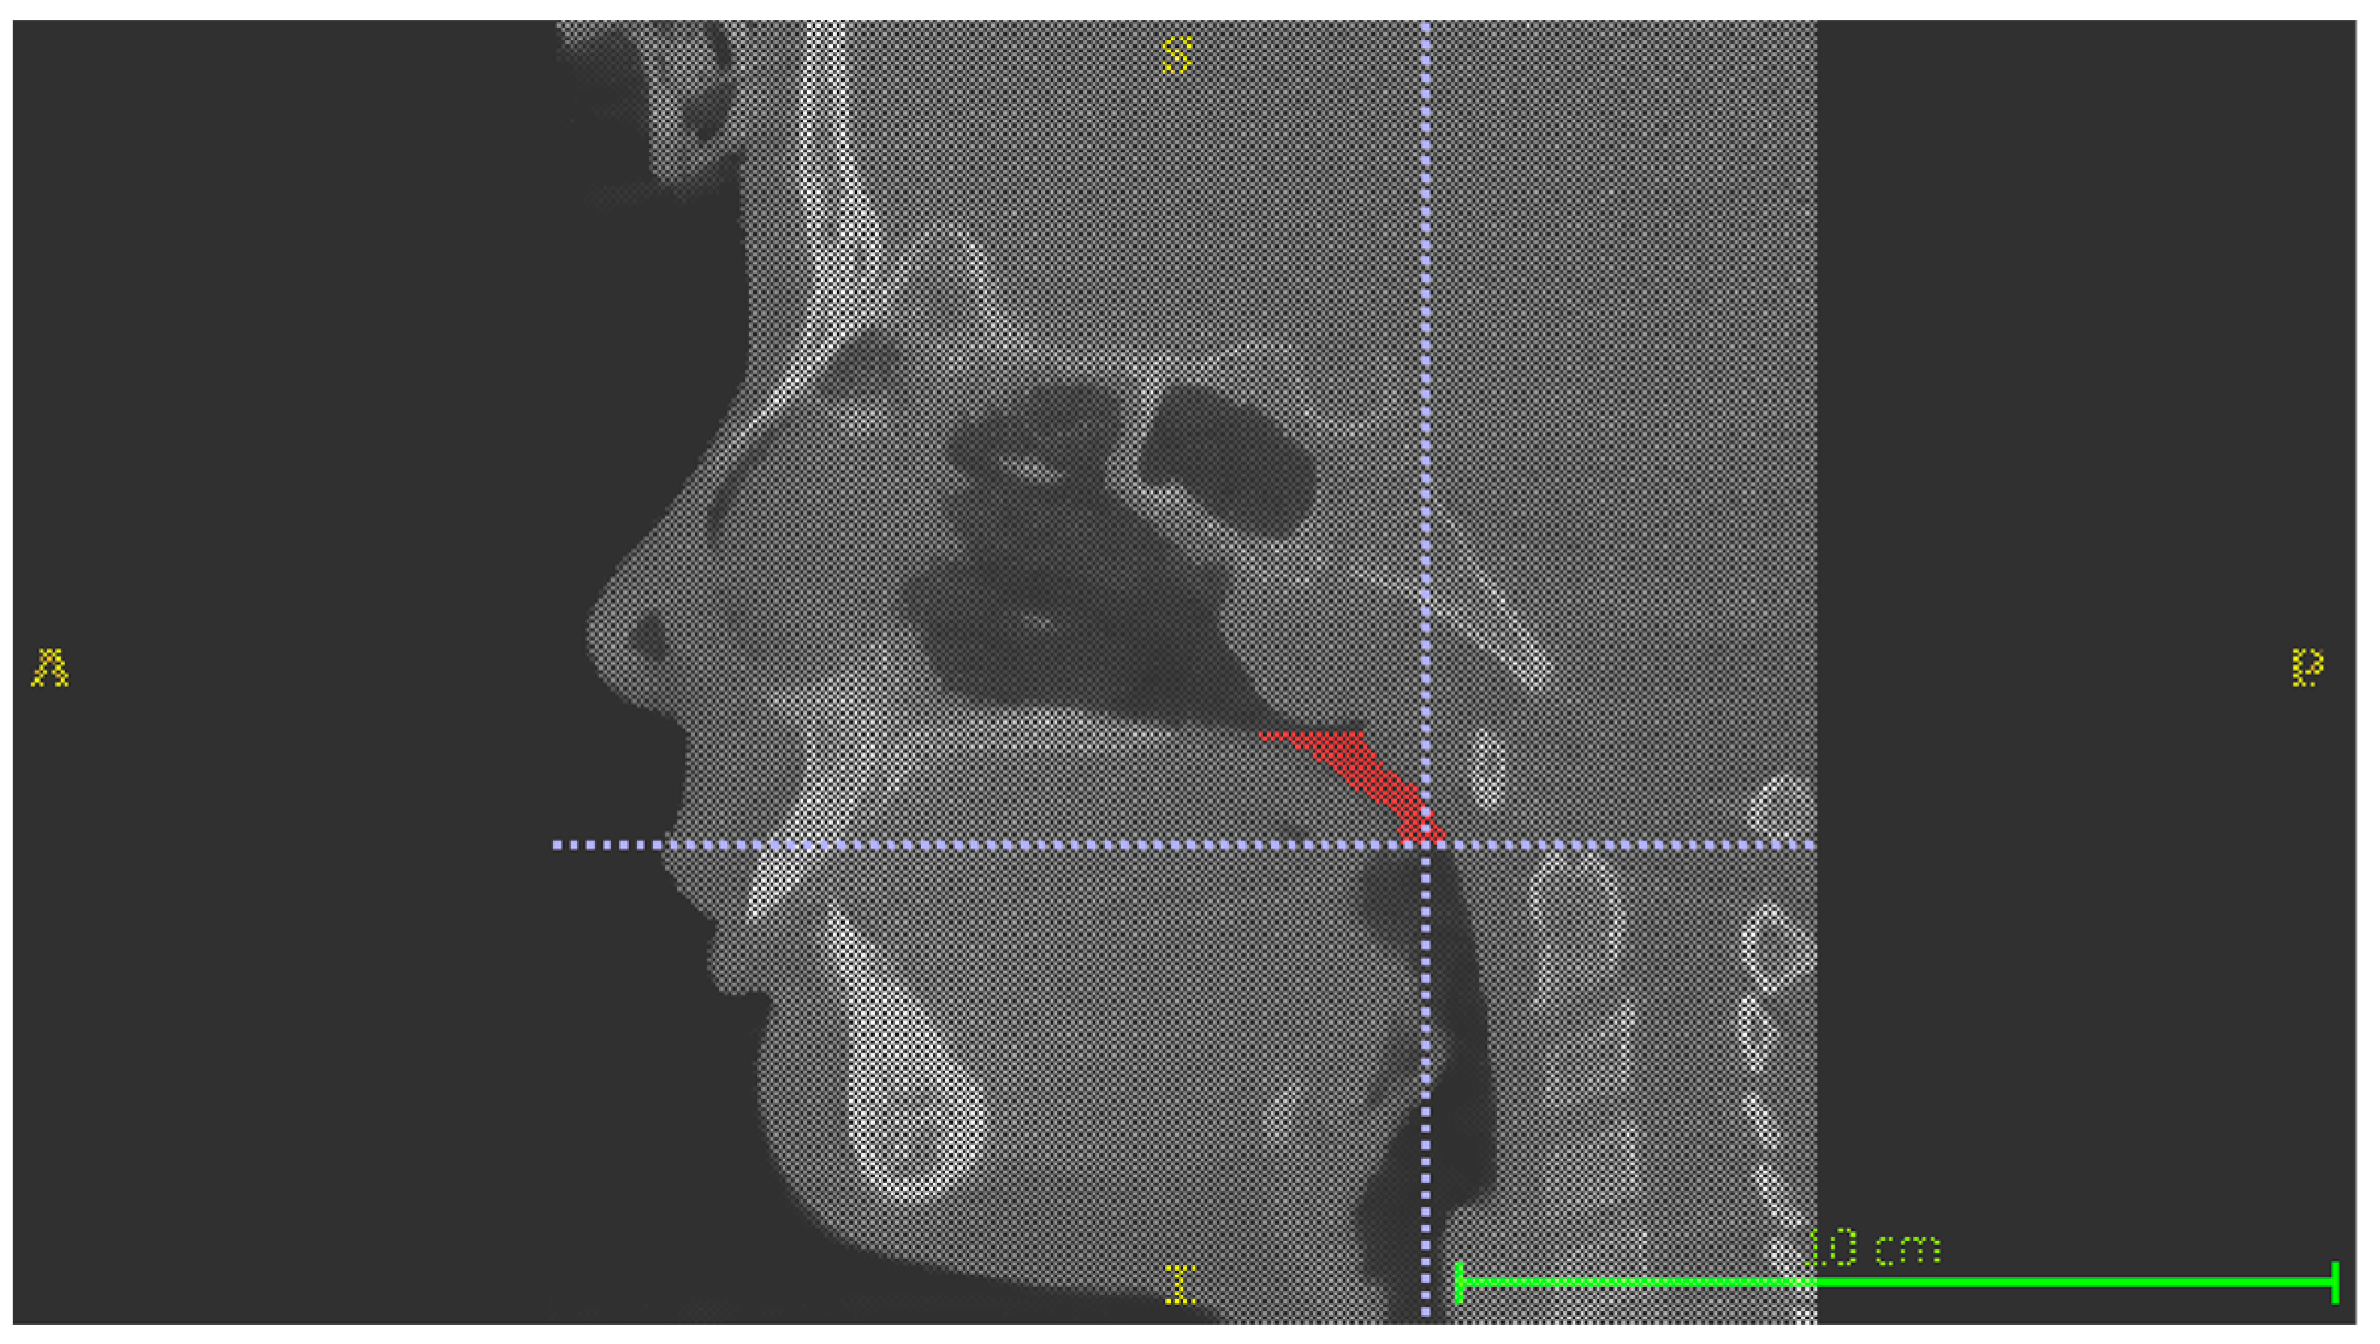

- Retropalatal volume (RPV), limited superiorly by a plane passing through posterior nasal spine and inferiorly by a plane passing through the most postero-inferior point of the soft palate (Figure 1);